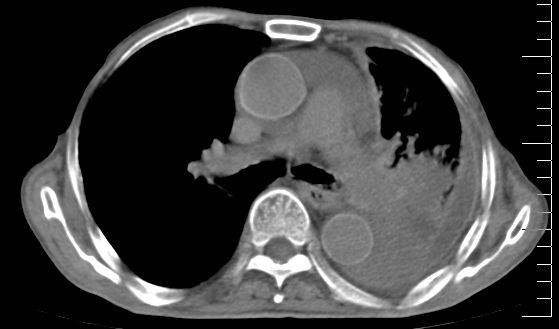

标题: CT10141:男、84岁,咳嗽、咯血1年。 [打印本页]

标题: CT10141:男、84岁,咳嗽、咯血1年。

支持左侧中央型肺癌伴下叶肺不张\\纵隔淋巴结转移.左侧包裹性胸腔积液\\心包积液.左侧少量胸腔积液..慢性支气管炎伴部分间质纤维化.

支持:左侧中央型肺癌伴下叶肺不张\\纵隔淋巴结转移.左侧包裹性胸腔积液\\心包积液.左侧少量胸腔积液..慢性支气管炎伴部分间质纤维化.另:支气管分支根部明显阻塞 狭窄,内膜凸凹不平,提示内膜增生物。

咯血病史较长,左肺下叶实变,体积未明显缩小,隐约可见血管影及坏死阴影,双肺门及纵隔淋巴结增大,心包增厚积液,纵隔右移位,单侧胸腔积液,首先考虑:大叶型肺泡癌伴纵隔心包转移。

左肺中心性肺癌并左肺下叶肺不张,纵隔淋巴转移、同侧胸腔及心包积液(转移)。